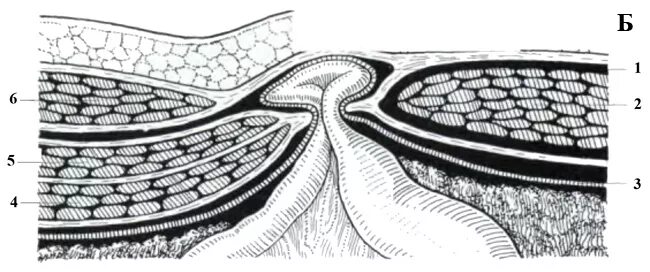

Грыжа спигелиевой линии